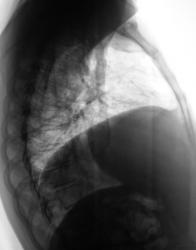

Два года тому поциентке произведена мастэктомия по поводу рака молочной железы. Направлена врачом онкологом (из области) для рентгенографии органов грудной полости. Произведено исследование.

Картина новообразования справа на верхушке, периферического, отсутствие переднего фрагмента 4 ребра справа, релаксация или приподнятость правого купола диафрагмы. Если при рентгеноскопии наличствует парадоксальная подвижность диафрагмы - парез диафрагмального нерва - мета в средостение, если нет - УЗИ печени - искать причину приподнятости купола там.

Как Вам второй вариант: после мастэктомии часто проводят лучевую терапию на над-подключичные л/узлы на стороне опухоли (в данном случае справа), естественно в поле облучения попадает в/доля легкого, где развивается сначала пневмонит, затем фиброз, возможен цирроз. Эти изменения очень вариабельны и зависят от индивидуальной чувствительности. На снимке, кстати, правый корень подтянут вверх, трахея подтянута вправо, в/доля уменьшена в объеме и неравномерно уплотнена. С чего бы этому быть при периферическом образовании? Касательно переднего отрезка 4 ребра справа - он действительно четко не прослеживается, но прозрачность легочного фона в этой зоне повышена, думаю, что снимок на этом участке "перебит" из-за того, что нет молочной железы. Рекомендую уточнить анамнез на предмет лучевой терапии, поднять снимки из архива, если нет такой возможности или остаются сомнения - направить на КТ. На передний отрезок 4 ребра справа требуется сделать прицеленый снимок.

Насчет ребра: патология там - безусловно есть, оно выпадает из реберного ряда уже на уровне приблизительно средней подмышечной линии...

На мой взгляд, скорее всего здесь имеет место постлучевой фиброз в верхней доле справа с уменьшением объема части легкого. Но для исключения новообразования я бы порекомендовал пройти КТ. Рисковать не стоит.

Затенение в S1, не похоже на перферический рак т.к. последнее всё таки узловое образование.Трахея перетянута вправо- скорее это постлучевой фиброз ( хотя картина несколько необычная, т.к. как правило,при лучевом фиброзе тени тяжистого характера).Нужно КТ( в4 ребре патология).